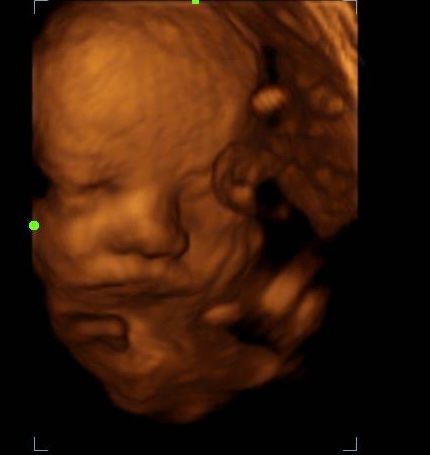

2d, 3d,4d & HD live

At your appointment, we connect directly to your home TV via HDMI, so everyone can enjoy a crystal-clear view. You’ll receive printed keepsake photos in the mail, plus digital images and video recordings delivered straight to your email.

Enjoy a private, affordable ultrasound from the comfort of your home, perfect for moms between 7–41 weeks. Share the moment with loved ones by connecting directly to your TV for real-time viewing in 2D, 3D, or 4D. Ideal for baby showers or gender reveal parties!